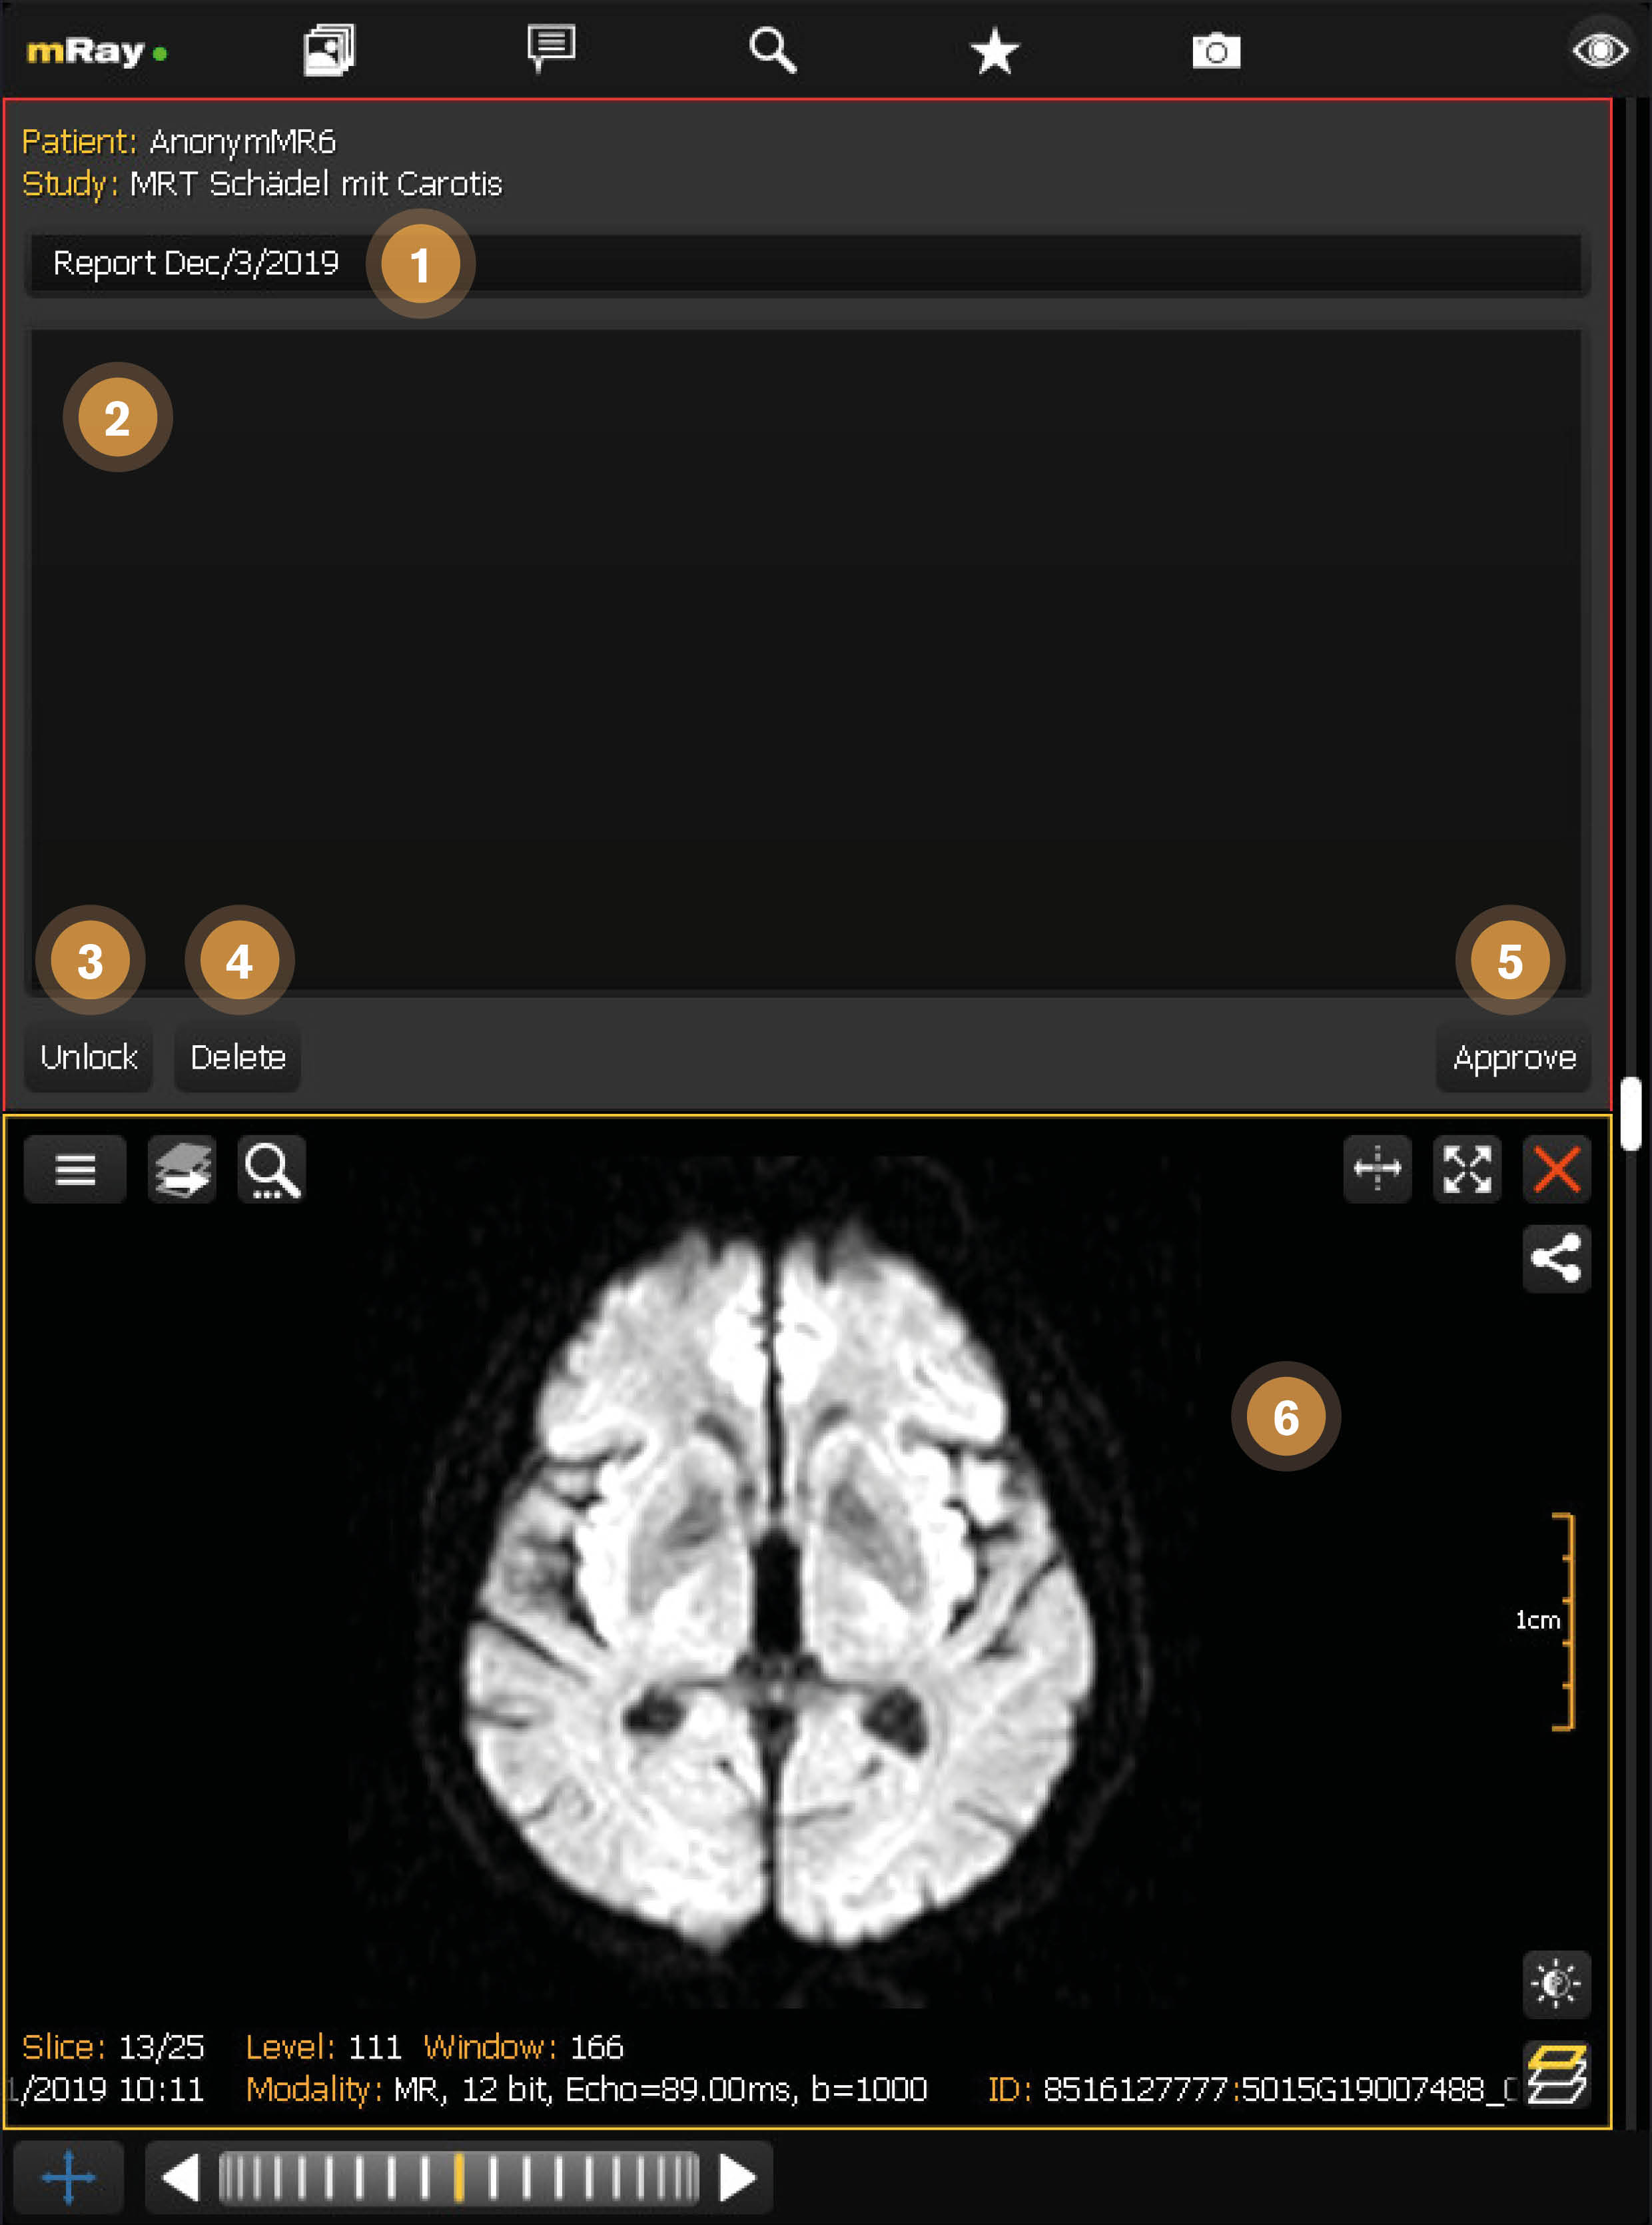

12.3. Draft editing view

After a draft is created it opens right next to the associated series. The patient and study information is filled automatically and the report title is prefilled from the current date. While the report is open it is locked for the current user, which means that no other users can edit it. This avoids multiple users working on the same draft performing conflicting changes.

-

Report title: The title for the structured report. Is prefilled with the current datum.

-

Report content: The content for the structured report e.g. a diagnosis or any other clinical information.

-

Unlock draft: Unlock this draft and allow other users to work on this draft.

-

Delete draft: Delete this draft. It will disappear for all other users aswell.

-

Approve draft: Finalize the current draft and create the structured report. After this action you can’t modify the report anymore.

-

Associated study: Displays the study that is associated with this report.